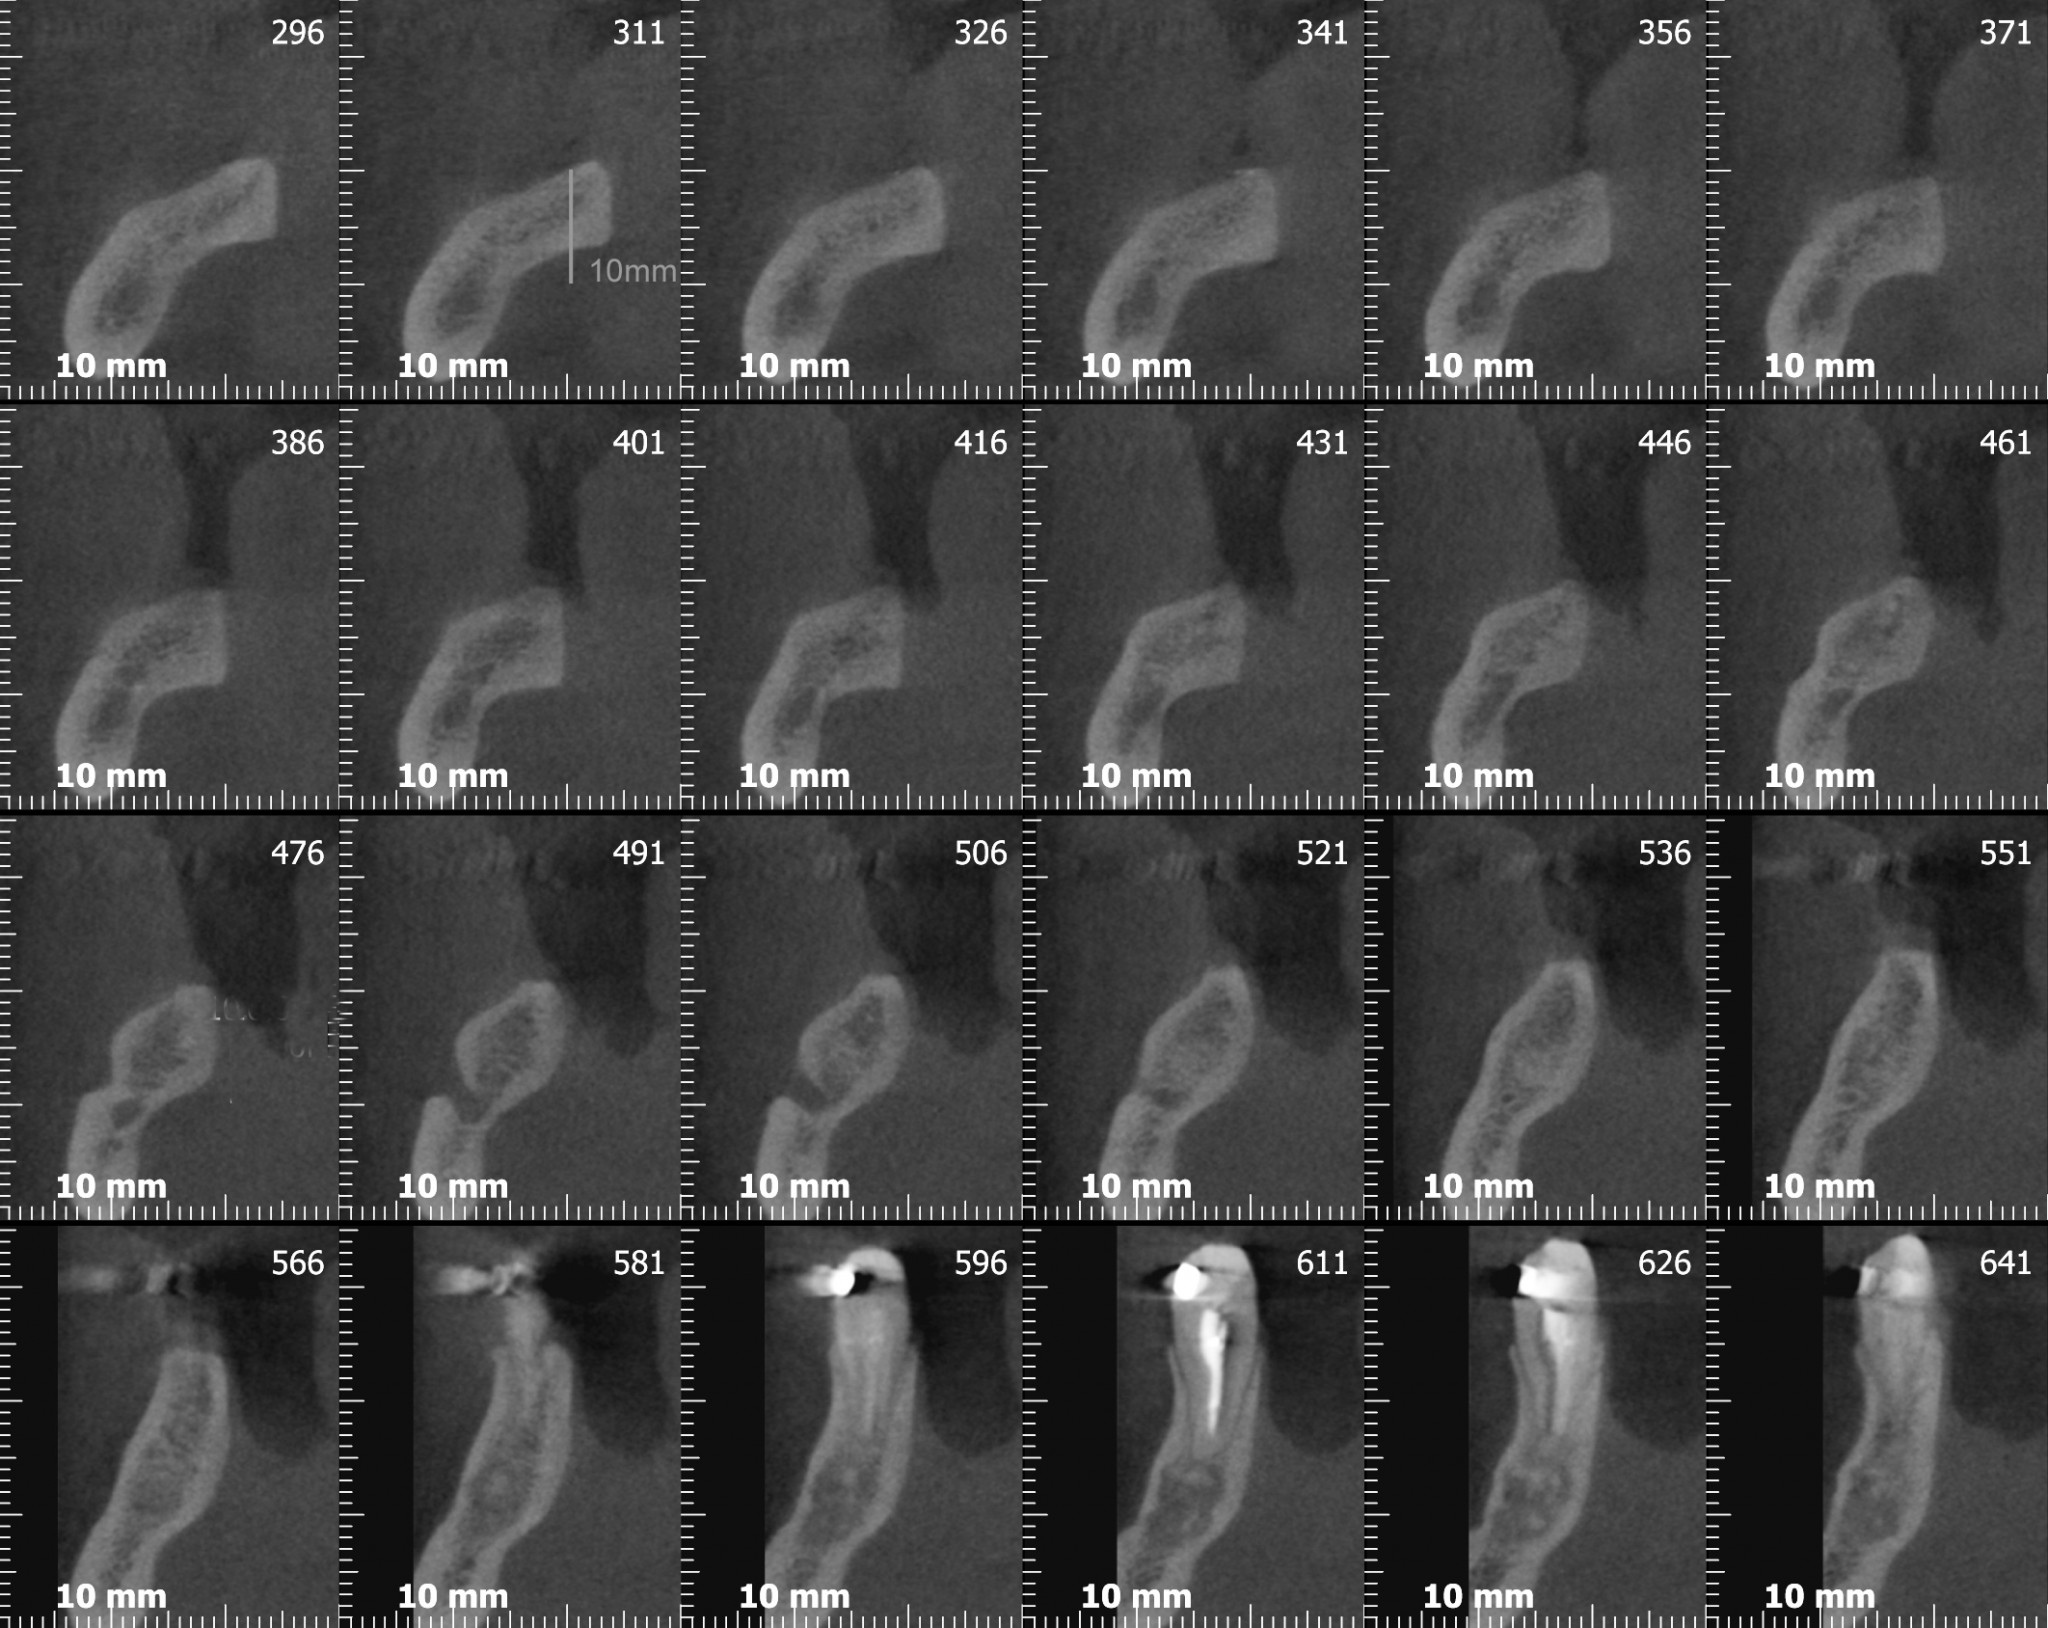

Adesso andiamo a vedere la cone-beam che sicuramente, secondo qualcuno, si sarebbe potuta evitare….

Se avessimo messo un impianto da 10mm nella zona del sesto con un asse protesicamente corretto avremmo proiettato tre o quattro millimetri delle nostre frese rotanti nella loggia sottomandibolare con tutti i danni potenziali che questi avrebbe potuto generare (se non l’hai ancora fatto vai poi a leggere l’articolo che ho linkato prima!).

Il signor Franco, nostro paziente da quasi dieci anni, qualche mese fa ha finalmente deciso di mettere gli impianti che gli avevamo proposto nel lontano 2007. Già dalla foto dovresti notare una marcata atrofia verticale e orizzontale. Come mio solito faccio fare una radiografia tridimensionale per progettare l’intervento in sicurezza e spiegare al paziente esattamente cosa andrò a fare durante la seduta chirurgica…

Ora guarda attentamente…….

….Ancora….

Cosa vedi? Ok, una bella atrofia orizzontale, associata ad una modesta atrofia verticale. Come possiamo trattare una atrofia verticale associata ad una orizzontale? (rimanendo all’interno dell’evidence based medicine per carità!)

Avevi notato questo? Dai tagli della cone-beam si nota chiaramente una variante anatomica abbastanza importante: un foro mentoniero accessorio posizionato più o meno a metà tra la cresta e il foro primario, diciamo circa 7 mm apicalmente alla cresta, dal quale emerge un ramo di diametro rilevante del nervo alveolare inferiore. Chissà a quale parte del mento o del labbro porta le sensibilità quel piccolo ramo!? Diciamo che per mantenere immacolato il mio palmares medico legale preferisco non scoprirlo!

Infatti ben poco sotto il livello della cresta compare l’infame…

Se lo lasciamo lì ovviamente non possiamo ricostruire un bel niente, ti faccio allora vedere come ho risolto io la situazione, ma a parte il tecnicismo chirurgico spero che il messaggio ti sia chiaro: